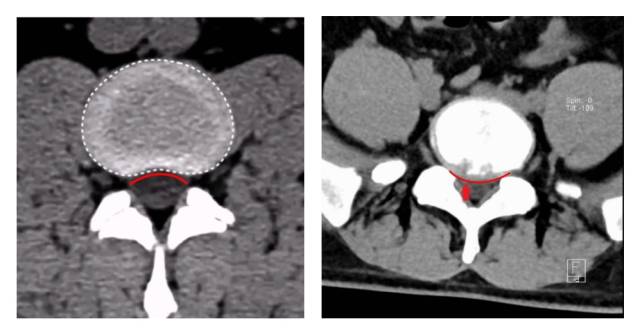

广医三院脊柱外科副主任医师王簕为小阳做了详细的检查,经CT、MRI检查后发现,小阳的腰5/骶1椎间盘膨出并偏右后方突出,右侧侧隐窝变窄,右侧神经根受压。

图左:正常腰间盘CT,椎体的后缘弧形向上。图右:小阳的腰间盘CT,椎体的后缘弧形向下,腰5/骶1椎间盘膨出并偏右后方突出。 受访者供图